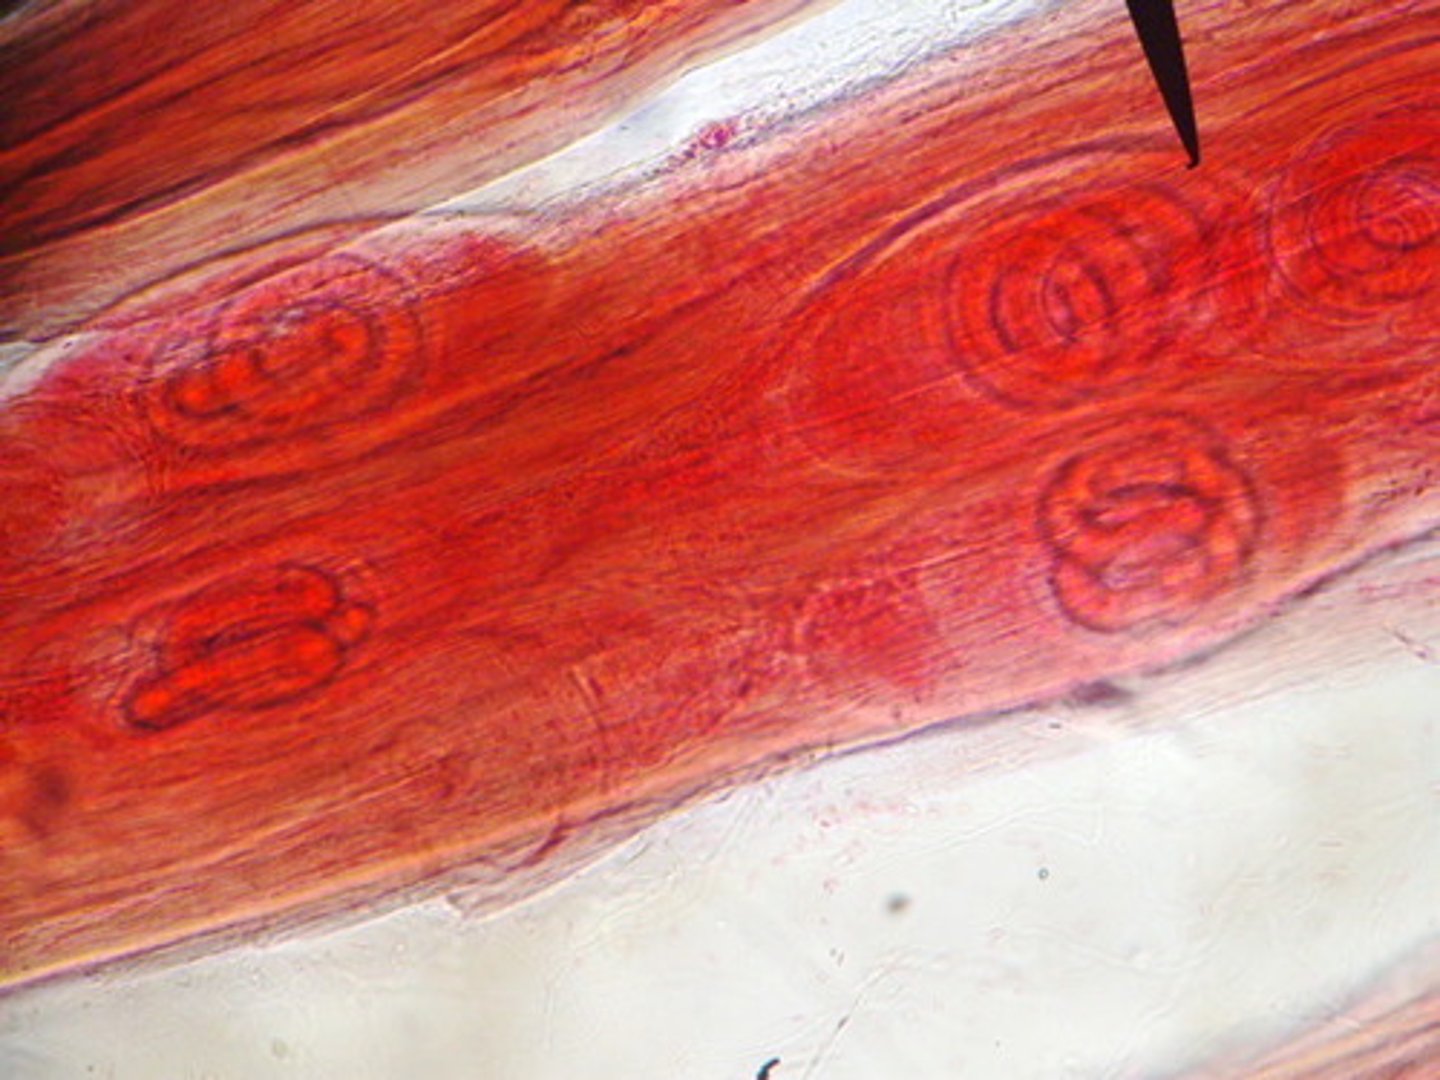

trichinella spiralis

-zoonotic nematode

-undercooked meat like pork and bear

-larvae released into intestine and mature and go into circulation

-can be asymptomatic if light

-larvae migrate into MUSCLE tissue! leading to CNS involvement and myocarditis!

-Muscle Encystment leads to myalgia and weakness

*we look at muscle tissue!